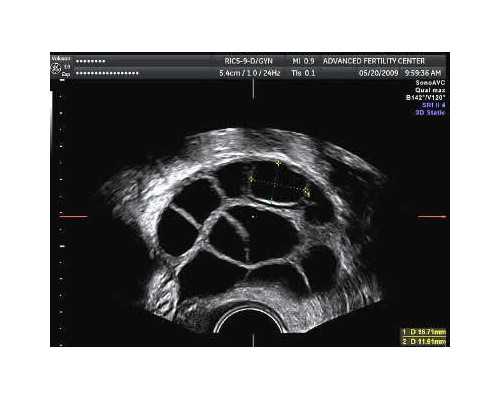

广东省生殖医院优生遗传首席专家郑立新解释,我们每个人都有46条染色体,其中Y染色体为男性所特有,虽然它看起来个头比较小,但是功能可不小,在男性精子发生过程中发挥至关重要的作用。Y染色体长臂上有影响精子发生的无精子因子(AZF)区域,包括AZFa、AZFb、AZFc三个区域,这些区域的缺失可能导致男性少精、弱精、无精。其中AZFc区的缺失最为常见,约占80%,表现为少精、弱精、无精都有,可呈进行性生精功能障碍。

Y染色体长臂上有影响精子发生的无精子因子(AZF)区域,包括AZFa、AZFb、AZFc三个区域,这些区域的缺失可能导致男性少精、弱精、无精。其中AZFc区的缺失最为常见,约占80%,表现为少精、弱精、无精都有,可呈进行性生精功能障碍。